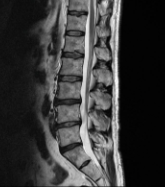

허리디스크 증상

허리디스크는 척추 디스크가 손상되어 디스크 내부의 젤 상태의 물질이 디스크 외부로 누출될 때 발생하는 질환입니다. 이러한 디스크 누출은 신경 자극을 유발하며, 이에 따라 다양한 증상이 나타날 수 있습니다.

- 디스크의 손상: 디스크는 척추의 각 뼈 사이에 위치하고 있으며, 뼈를 서로 붙이고 충격을 흡수합니다. 디스크가 손상을 받거나 균열이 발생하면 인접한 신경과 충돌하여 통증을 유발할 수 있습니다.

- 추간판의 변형: 추간판은 척추의 뼈 사이에 위치하고 있으며, 뼈를 서로 붙이고 충격을 흡수합니다. 추간판이 변형되거나 압박을 받으면 통증이 발생할 수 있습니다.